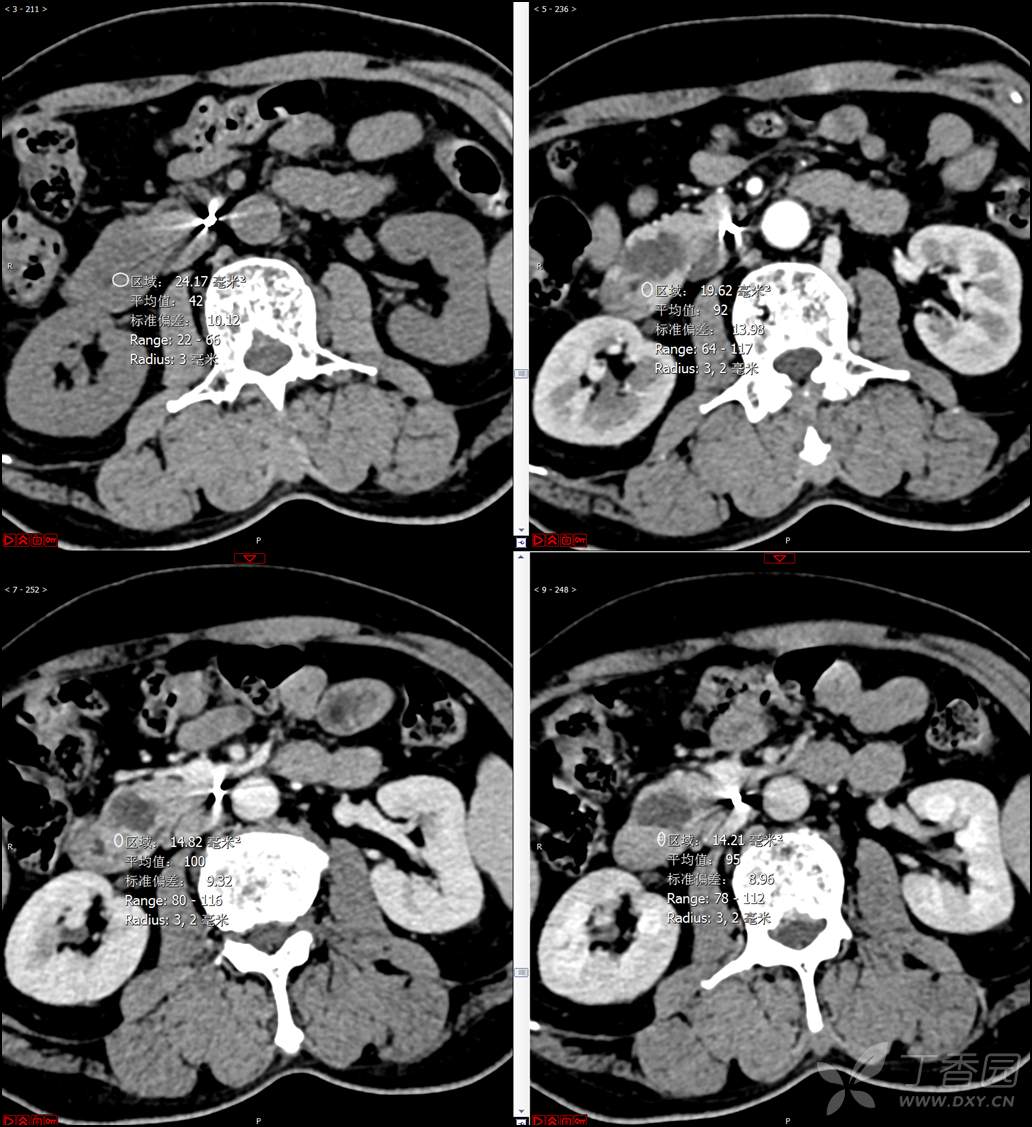

【影诊笔记521】老年男性,黑便就诊,请分析~『回帖即可查阅答案』

患者年龄:67岁

主诉:黑便1周。

现病史:患者1周前无明显诱因出现黑便伴头晕、心慌,无胸闷、胸痛,后仍间断黑便,2022-10-27就诊于某市中医院,行胃镜检查示:十二指肠溃疡伴出血,给予止血、抑酸等对症治疗,效果欠佳。今为行进一步治疗就诊于我院急诊,门诊完善新型冠状病毒核酸检测后以“十二指肠溃疡伴出血”收入我科。患者自发病以来,神志清,精神可,未进食,睡眠可,小便未见异常,黑便,近期体重无明显增减。